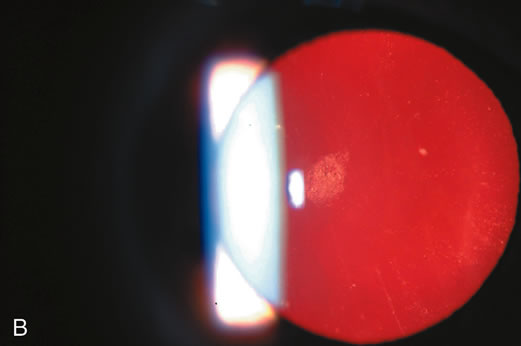

Fig. 1. Cortical cataract using (A) direct illumination (B) retroillumination. Cortical cataracts usually start in the lens periphery and encroach into the visual axis (and interfere with central vision) only in later stages.

Retroillumination uses the light reflected from the fundus to highlight opacities. This is very useful in examining cortical and posterior subcapsular cataracts (Figs. 1, 3, 7, and 8). However, some cortical water clefts and early posterior subcapsular opacities may not be easily seen with retroillumination if they are not dense enough to cast shadows or only refract the retroilluminate light; these can be best seen with the broad beam. Using retroillumination on nuclear cataracts does not give much information because these usually do not cast shadows. However, as seen in Figure 2B, a change in the refractive index can be seen toward the center. Usually, the outline of the nuclear cataract can be seen as a result of a “magnifying lens” artifact. This is also easily observed during direct and indirect ophthalmoscopy. Several retroillumination cameras (modified slit lamps with the slit beam fixed for retroillumination and depolarizers built in to remove corneal reflex from the image) have been developed and are being used for documenting cortical and posterior subcapsular cataracts.49, 50